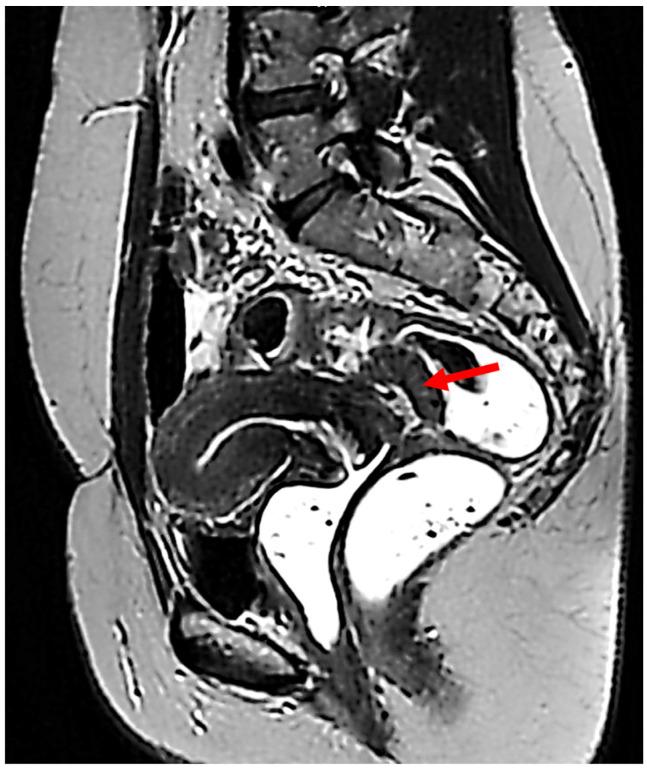

Endometriosis is a common gynecological disease that can occasionally be associated with malignant transformation. The most common site of malignant transformation is the ovary, but there can also be rare extragonadal endometriosis-associated malignancy sites, such as the intestines, rectovaginal septum, and abdominal wall. A low number of malignant degenerations of rectal endometriosis are described in the literature. However, the majority of these cases report endometrioid adenocarcinoma as the most frequent histopathological type of tumor. On the other hand, Müllerian clear cell carcinoma is sporadic. We present the case of a 43-year-old woman with clear cell carcinoma of the rectum, which developed on an endometriosis nodule, and the surgical outcome. Imaging of the case was performed by MRI. The patient was offered curative surgery. The pathology report confirmed a clear cell carcinoma developed on an endometriosis lesion, and immunochemistry helped in the characterization of the tumor. The patient developed a rectovaginal fistula. An ileostomy and surgical repair of the fistulous opening were performed, with a favorable postoperative recovery. Malignant transformation of endometriosis lesions is possible and should be taken into consideration. Müllerian clear cell carcinoma development within rectovaginal endometriosis is extremely rare.

子宫内膜异位症是一种常见的妇科疾病,偶尔可伴有恶性转化。恶性转化最常见的部位是卵巢,但也有罕见的性腺外子宫内膜异位症相关的恶性部位,如肠道、直肠阴道隔和腹壁。文献中描述的直肠子宫内膜异位症恶性退变病例较少。然而,这些病例中的大多数报告子宫内膜样腺癌是最常见的肿瘤组织病理学类型。另一方面,苗勒管透明细胞癌较为散见。我们报告一例43岁女性直肠透明细胞癌病例,该肿瘤发生于子宫内膜异位结节,并介绍手术结果。该病例通过磁共振成像(MRI)进行影像学检查。为患者实施了根治性手术。病理报告证实为发生于子宫内膜异位病变的透明细胞癌,免疫组化有助于肿瘤的特征性诊断。患者出现直肠阴道瘘。进行了回肠造口术及瘘口手术修复,术后恢复良好。子宫内膜异位病变有可能发生恶性转化,应予以考虑。直肠阴道子宫内膜异位症中发生苗勒管透明细胞癌极为罕见。